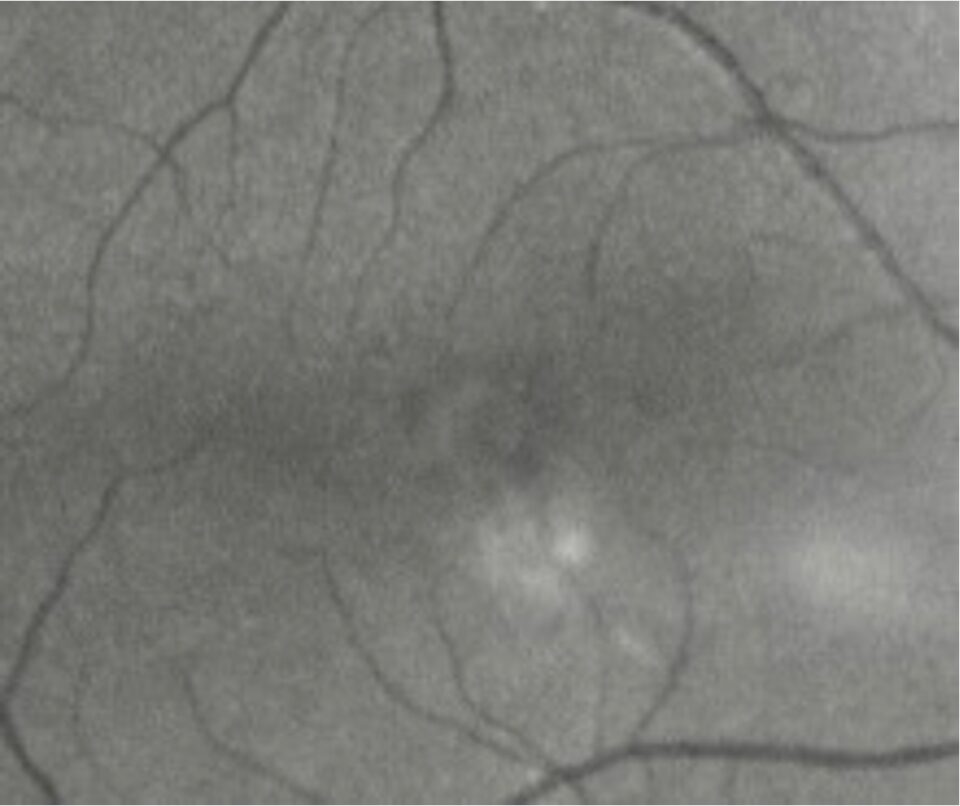

Case: Macular Pathology

A 67-year-old male attends your clinic with reduced vision OD.  He finds contours difficult to see and letters can also be difficult to distinguish.

The vision has worsened in the last half year and especially in the last month. It's uncertain whether he experiences any metamorphopsias.

BCVA half a year ago was 1.2 (6/5). Today it is 0.3 (6/20) (PH 0.3 [6/20]).

Anterior segment is without any indication of his reduced vision. Posterior segment has normal vasculature, optic nerve head and retina.